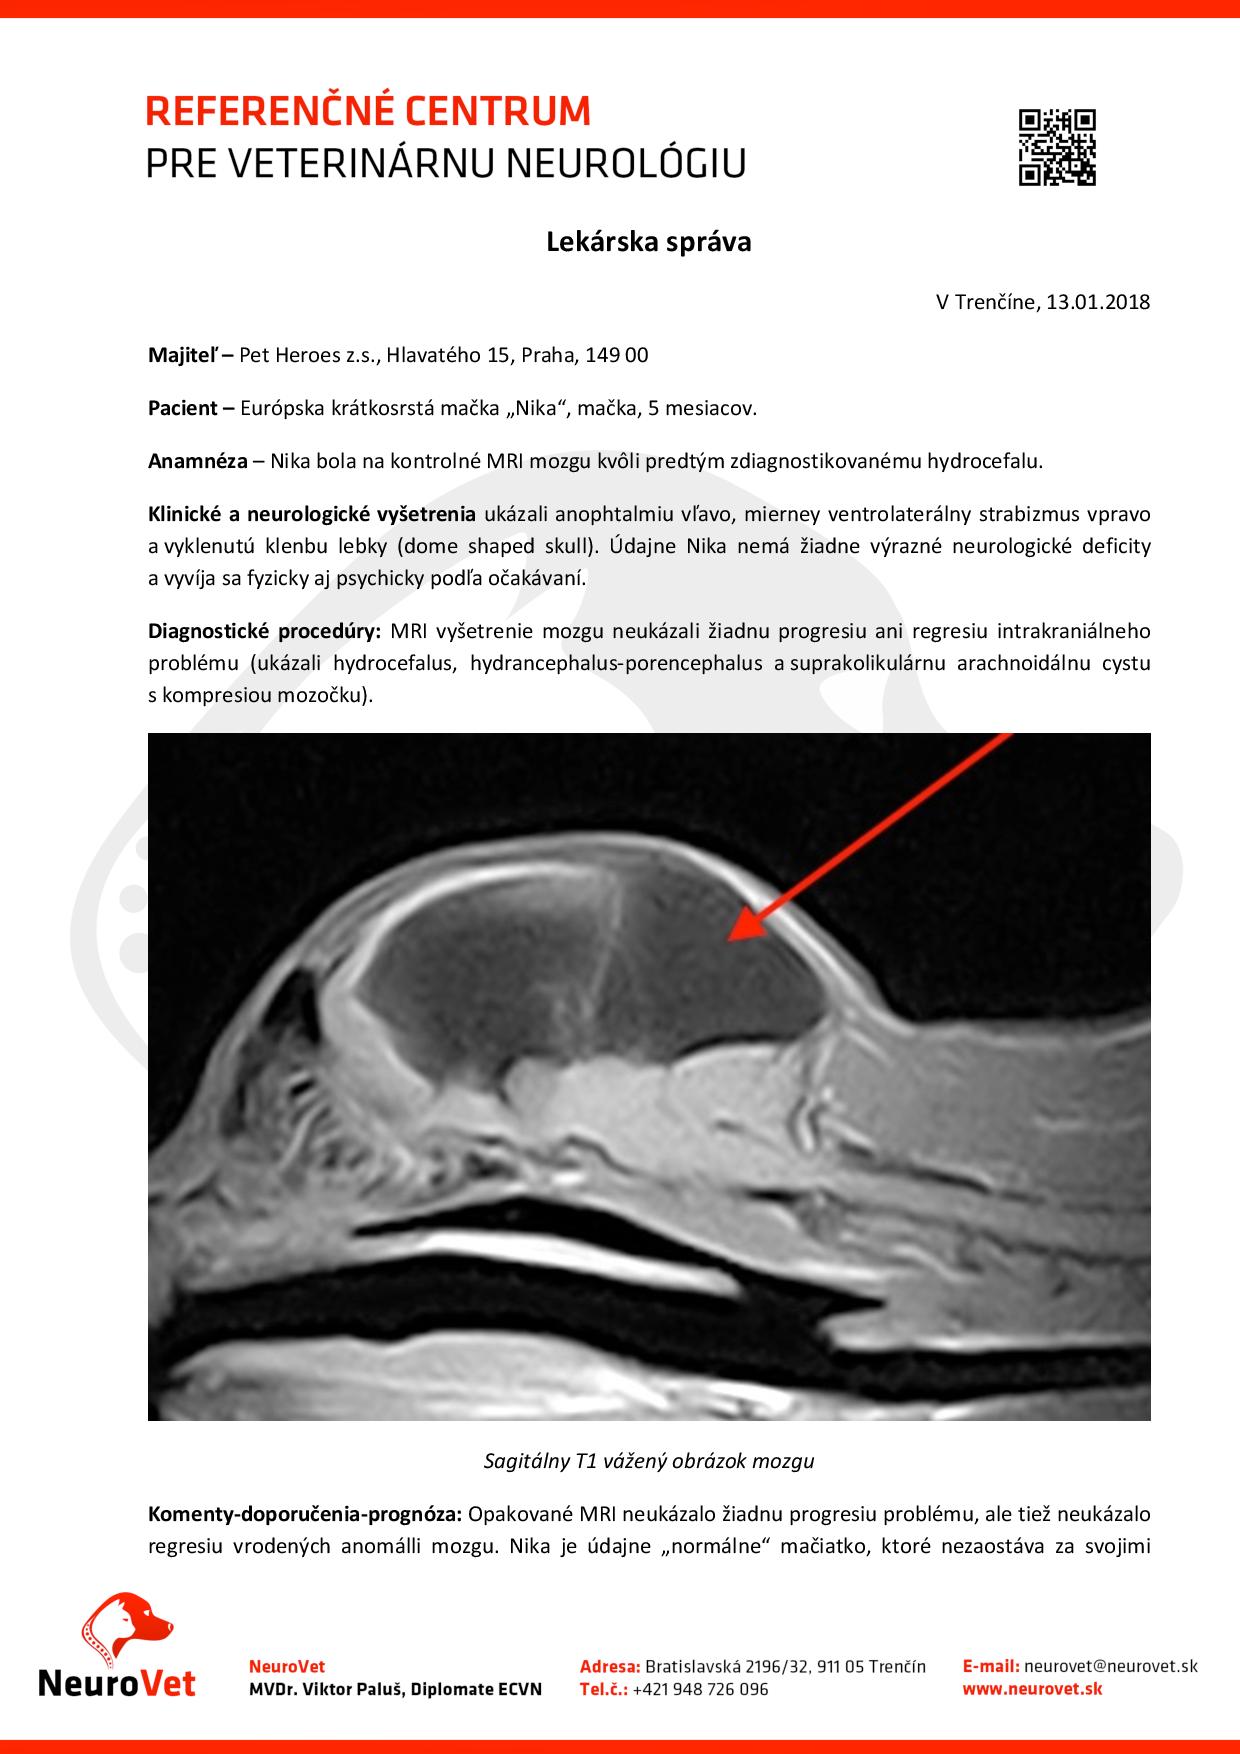

Původně to vypadalo, že je to způsobeno hydrocefalem – vznikem tekutiny, která nemá v hlavičce co dělat a že bude nutné, aby jí byla zavedena hadička, která dokáže tekutinu odčerpávat do těla, kde se o ni organismus postará. Poté, co podstoupila návštěvu u pana veterináře na Slovensku nám však vysvitla naděje, že Nika nebude operaci potřebovat.

Existovala zde totiž možnost, že Nikuška prodělala jako malinkaté koťátko panleukopenii a ta poškodila mozek natolik, že zůstal zakrněný. Jedinou možností, jak to zjistit, bylo udělat kontrolní MRI (jedno MRI v ČR měla již za sebou, tam ale nad touto variantou neuvažovali, možná je ani nenapadla), které mělo zjistit, jestli se mozek jakkoliv mění nebo zůstává stejný. Pokud byl zůstával stejný, znamenalo by to, že Nikuška by žádnou operaci nepotřebovala.

Díky spouště skvělých lidí se podařilo nasbírat dostatečné finanční prostředky na to, aby Nikuška mohla MRI podstoupit! A jaký je výsledek?Její diagnóza je nakonec Hydraencefalus – znamená to, že má sice v hlavě vodu, ale nic jí nedělá, netvoří se další tekutina a tím pádem není důvod operovat!

Problém v tuto chvíli je, že se u mozečku vytvořila cysta. Ta ale nemusí vůbec růst, ani nijak překážet. Kdyby začala mít problémy s koordinací, bude se muset přistoupit na opětovné vyšetření a možná operaci, ale pro tuto chvíli je Nikuška v pořádku a nepotřebuje žádnou operaci.